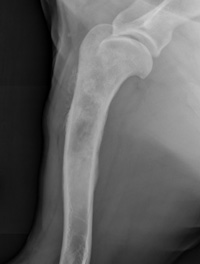

BONE CANCER IN DOGS - Csuanimalcancercenter.org

BONE CANCER IN DOGS Introduction Approximately 85% of bone tumors in dogs are osteosarcomas (osteo = bone, sarcoma = cancer). Osteosarcomas are highly aggressive tumors, characterized by painful local ... Fetch Document

Osteosarcoma - Lap Of Love

Osteosarcoma in Cats and Dogs This aggressive type of cancer can develop in any bone, but the legs account for 75-85% of affected bones. try to cure the cancer or simply manage pain and symptoms if a cure is not possible. ... View Doc

Canine Osteosarcoma - Bone Cancer In Dogs

Bone cancer. My worst fears were realized. (Osteosarcoma affects the front legs twice as often as the back legs.) The bone lesion was also large, and I knew that it had already spread to the lungs, ... Read Article

Osteosarcoma: The Nemesis Of Large Breed Dogs

To start, what is an Osteosarcoma? Osteosarcoma is a cancer of bone, which has its origin in the bone forming cells called osteoblasts. The most important sign is bone pain. If the legs are affected the early sign are generally lameness, ... Return Document